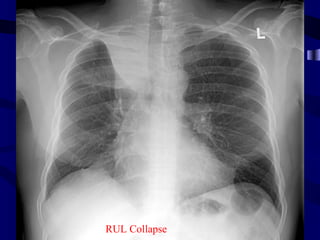

Rul collapse

SIGNS OF COLLAPSE DIRECTSIGNS: • Displacement of fissures • Loss of aeration • Vascular & bronchial signs INDIRECT SIGNS: • Mediastinal & Hilar displacement • Elevation of Hemidiphragm • Compensatory hyperinflation